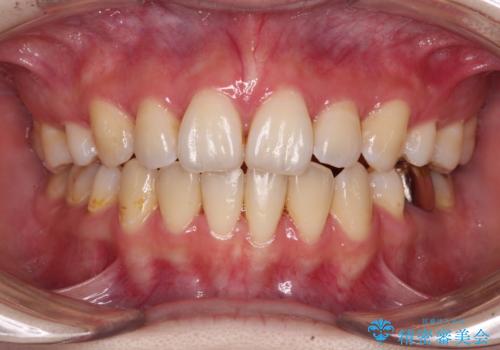

口元を下げてすっきりさせたい ワイヤー抜歯矯正で口元の改善